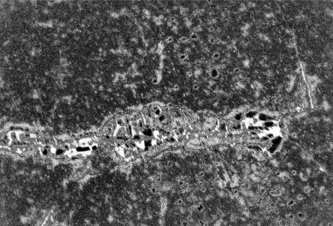

) Photo Neuróny asi nevyzerajú tak, ako sme si mysleli

Neuróny asi nevyzerajú tak, ako sme si mysleli